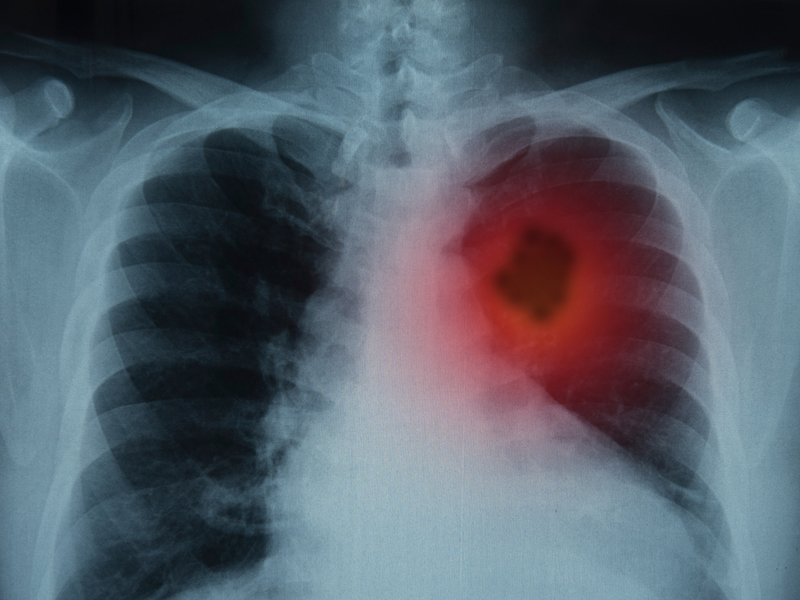

二、睡覺出現4種異常,或是肺癌信號

肺癌並不是無跡可尋,尤其是睡覺時,出現這幾種信號,就要警惕可能與癌症有關: